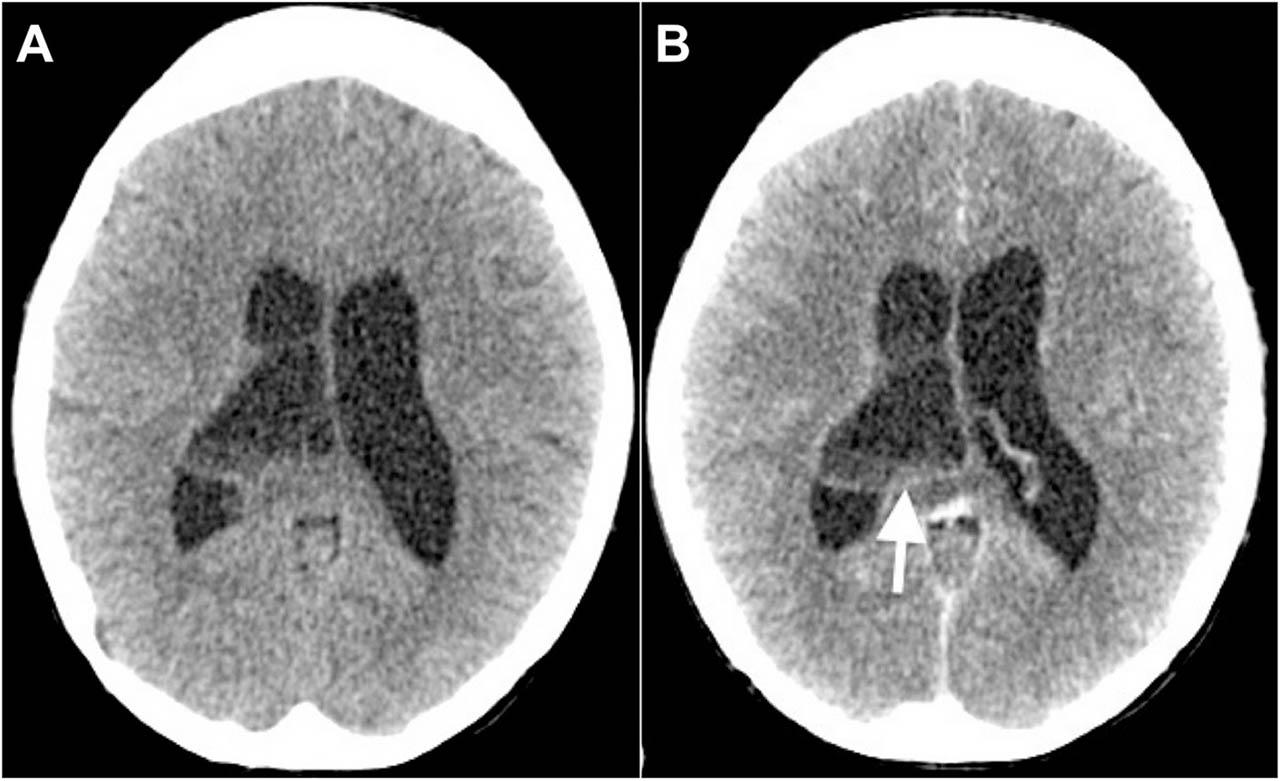

Figure 1

Axial images of (A) plain and (B) contrast computed tomography of the brain show a cystic lesion within the right lateral ventricles with sediments and septations within. There is also a minimal rim enhancement of the wall (arrow) and dilatation of both lateral ventricles consistent with hydrocephalus.